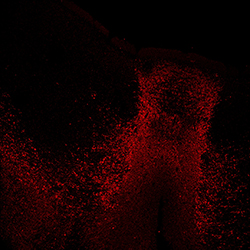

An anatomical analysis of the developing human midbrain from 6 post-conceptional weeks (PCW) to 22 PCW reveals increased tissue complexity, characterized by the emergence of dopaminergic nuclei, as highlighted by immunofluorescence analysis for tyrosine hydroxylase (TH).

TH

11PCW human midbrain